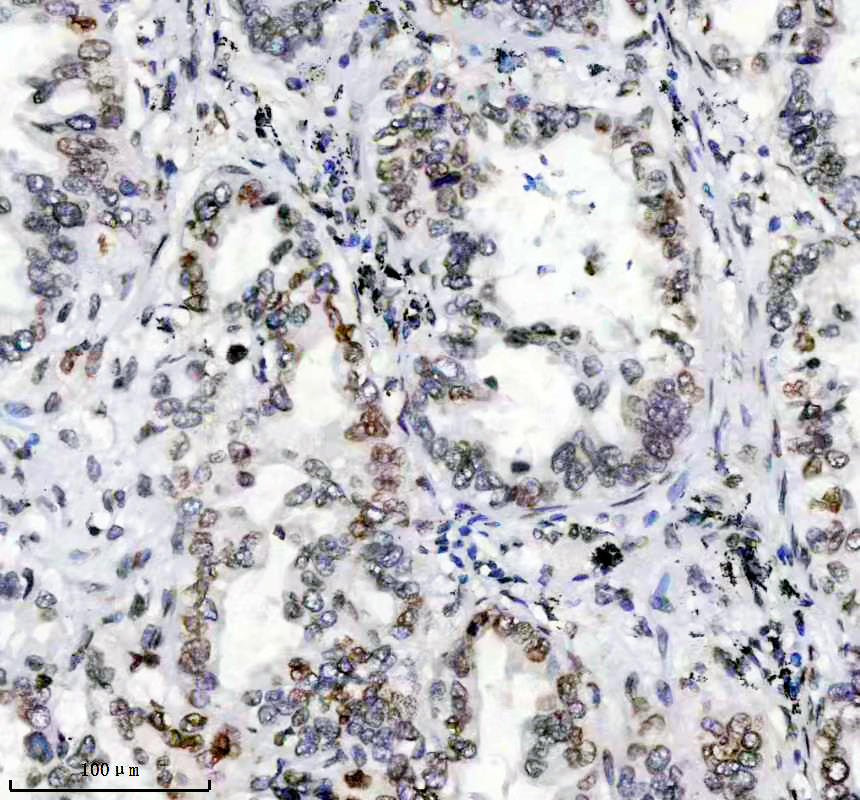

IHC analysis of Lamin A/C using anti-Lamin A/C antibody (BM4105).

Lamin A/C was detected in a paraffin-embedded section of human breast cancer tissue. The tissue section was incubated with rabbit anti-Lamin A/C Antibody (BM4105) at a dilution of 1:200 and developed using HRP Conjugated Rabbit IgG Super Vision Assay Kit (Catalog # SV0002) with DAB (Catalog # AR1027) as the chromogen.